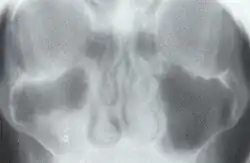

1930 entwickelte er die Grundlagen der Tomographie, die er selbst als axiale transverse Röntgen-Stratigraphie bezeichnete.[2][3][4] Dazu ließ Vallebona eine Röntgenquelle und einen Film gegenläufig um einen Patienten laufen, so dass nur die im Drehpunkt liegende Ebene scharf abgebildet wurde. Die weiteren Ebenen vor und hinter der scharf abgebildeten Ebene erschienen auf dem Röntgenbild aufgrund ihrer Bewegungsunschärfe als Verwischungsstrukturen. Moderne Tomographen verwenden einen Computer, um jene Verwischungsstrukturen aus dem Röntgenbild herauszurechnen. 1970 wurde A. Vallebona mit der Röntgen-Plakette ausgezeichnet.